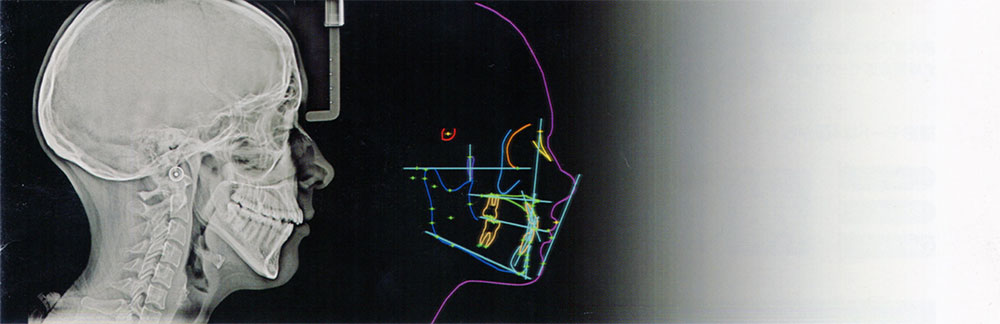

Cephalometric Evaluation of Facial Height Ratios and Growth。cephalometry-ceph-tooth-dental。矯正医選びのプロ視点①CT・セファロレントゲンによる精密な診断。「Radiographic Cephalometry」DVD付き書き込みはありません。A series of cephalometric radiographs depicting the patient。DVDは未開封です。成田崇矢の臨床『腰痛』 裁断済み 運動と医学の出版社。写真にて状態をご確認ください。健康・医学 Patient Blood Management Cardiac Surgery。中古品、自宅保管にご理解お願いいたします。医療・看護専門書19冊セット(バラ売り可)。#歯科#矯正#セファロ